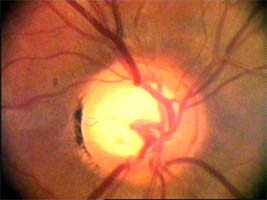

Tento terč má širokou cirkulární peripapilární atrofii, která opticky vytváří falešný dojem širokého neuroretinálního lemu, zvláště nasálně.

Očekávali byste protažení exkavace k hornímu pólu terče, jak nám ukazuje tento snímek z tomografu HRT II.

exkavace levé oko

Na kterém oku je exkavace větší, na pravém nebo na levém? Podle pohledu na fotografie jistě na levém.